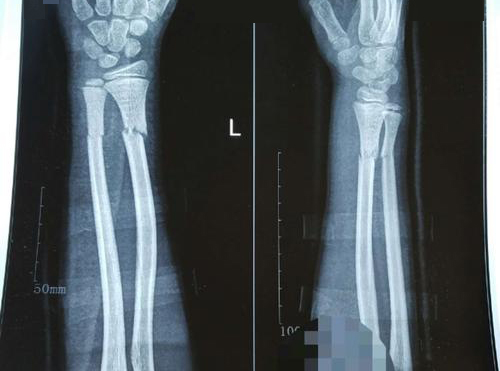

诊断病情:上桡骨骨折

主诉:手腕疼痛肿胀,关节活动困难

孙先生一天前由于不慎跌倒时手掌着地,当即感到手腕疼痛,几小时后出现局部肿胀、疼痛,手腕关节活动受限,遂来我院检查,发现关节有明显错位,诊断为上桡骨骨折。